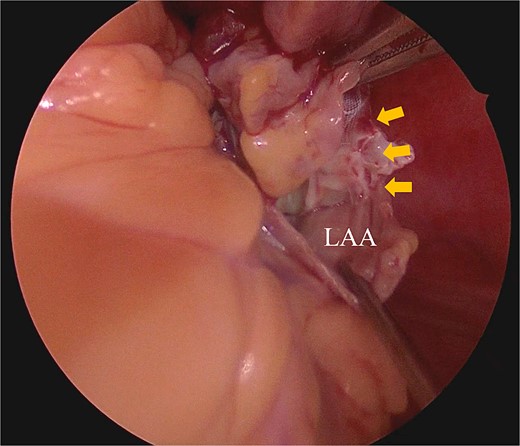

Under general anesthesia, the chest was entered through a median sternotomy. Cardiopulmonary bypass was established with dual venous drainage. The aorta was cross-clamped, and cardiac arrest was achieved through antegrade cardioplegia. Upon right atriotomy, the right atrial mass was attached to the ventral wall of the RA; it was easily excised by scissors. Subsequently, palpation of the LAA confirmed that the WATCHMAN device was adequately deep-seated and there was enough room from the base of the LAA. An incision was made at the base of the LAA, and the WATCHMAN device was excised along with the LAA (Fig. 5). The LAA was closed with direct suturing. The pathological examination confirmed the right atrial mass to be a thrombus. Postoperatively, anticoagulation therapy with warfarin was initiated. The patient was discharged from the hospital 13 days postsurgery. The echocardiogram performed 6 months postoperatively that did not reveal any recurrence of mass.

Intraoperative finding shows that the piece of WATCHMAN device can be shown from an external incision of LAA.